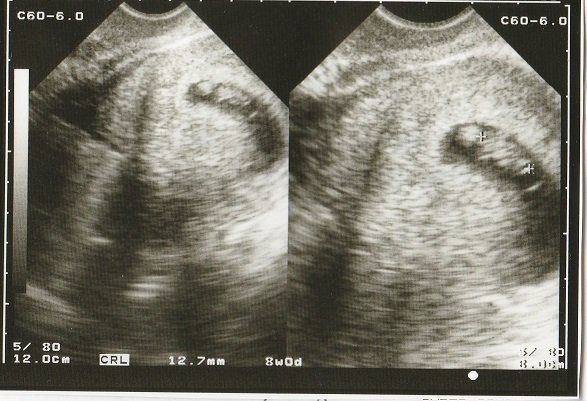

妊娠8週目のエコー写真 10mm以上に成長

CRL(頭殿長=頭からおしりまでの長さ)が10mmを超えました。

順調に大きくなっていますが、まだまだ「大丈夫だろうか?」という不安が大きかった時期。